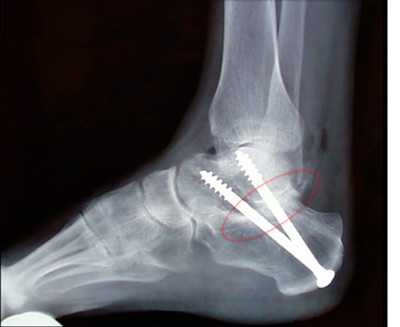

Пациент М. 1980 г.р., травму получил при падении на стопы с высоты 1,5 метра. Лечился по месту жительства (в травмпункте районной больницы) консервативно в гипсовой повязке в течение 14 дней. Консультирован в травматологическом отделении ФГБУ «УНИИТО им. В.Д. Чаклина» Минздрава РФ, предложено оперативное лечение. При поступлении кожные покровы стопы чистые, без признаков воспаления и сдавления тканей. Стопа отечна, уплощена. На рис. 1 представлены рентгенограммы пациента. Прооперирован через 2 недели после травмы. Операция состоит из двух этапов. Первый этап заключается в наложении дистракционного аппарата. Проводятся две спицы 1,8 мм во фронтальной плоскости: первая через нижнюю треть диафиза большеберцовой кости, вторая через бугор пяточной кости (рис. 2). Спицы фиксируются в дистракционном аппарате, выполненном из двух полуколец, соединенных между собой двумя телескопическими тягами. Особое расположение полуколец, фиксация спиц на концах полуколец, крепление кронштейнов для телескопических тяг обеспечивает тракцию пяточной кости в необходимом направлении с использованием минимального количества спиц и внешних опор при сохранении необходимого поля обзора для проведения рентгенологического и визуального контроля репозиции и фиксации. Второй этап - закрытая элевация импрессированной суставной поверхности и окончательная репозиция пяточной кости. Через разрез длиной до 1 см по латеральному краю ахиллова сухожилия (рис. 3) в месте его прикрепления к пяточной кости под соответствующий фрагмент подводится элеватор (рис. 4), манипуляцией которым устраняется смещение и выполняется провизорная фиксация спицами 1,5 мм (рис. 5). При сагиттальном раскалывании суставной фасетки целесообразно проведение одного-двух винтов субхондрально (рис. 6). Стержень вводится с дорзальной поверхности пяточной кости по ее оси через разрез до 2 см по предварительно сформированному остеотомом каналу (рис. 7, 8). Далее через проколы кожи с помощью кондуктора (рис. 9) выполняется запирание винтами с латеральной поверхности, внешнее устройство демонтируется. Достигнуто удовлетворительное стояние отломков (рис. 10).

Рис. 9. Внешний вид конечности после демонтажа аппарата и снятия кондуктора

Рис. 10. На рентгенограмме левой стопы в прямой и боковой проекциях определяется удовлетворительное стояние костных фрагментов на фоне металлофиксатора

Предлагаемый авторами способ оперативного лечения переломов пяточной кости является малотравматичным эффективным вариантом хирургического вмешательства, позволяющими профилактировать возможные типичные осложнения, такие как нагноения, и достигать сращения кости в физиологические сроки консолидации.